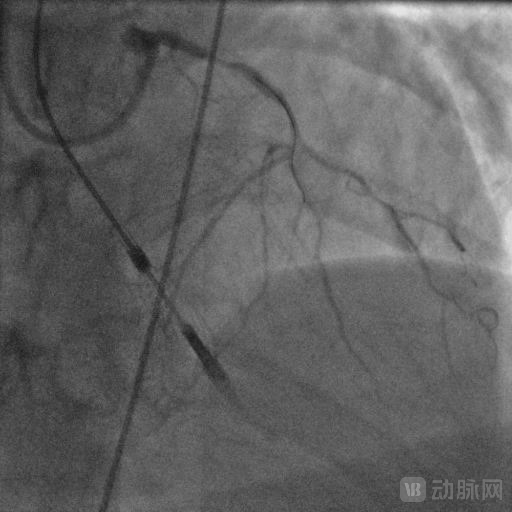

术中造影显示左主干远段原植入支架内再狭窄85%。前降支近段狭窄80%,前降支中段完全闭塞。第一对角支开口狭窄99%,第二对角支中段狭窄50%。左回旋支细小,开口完全闭塞。右冠状动脉近中段原植入支架内通畅,远段狭窄50%。

经过充分的术前评估,葛均波院士及其团队经右股动脉置入9F介入鞘,而后送入NyokAssist®至工作位后启动装置提供循环辅助支持并维持3.0 L/min流量,动脉血压由泵启动前85/50 mmHg升至120/80 mmHg左右,持续维持并开始PCI手术。

取EBU3.5指引导管至左冠口,在Expressman延伸导管及130cm APT微导管辅助下,采用Fielder XT-R导丝成功通过闭塞段送至前降支远段。取2.0*20mm、2.5*20mm球囊于前降支近段-远段病变处预扩张,前降支远段-近段串联植入2根支架。最后取2.0*20mm球囊于第一对角支开口病变处扩张。